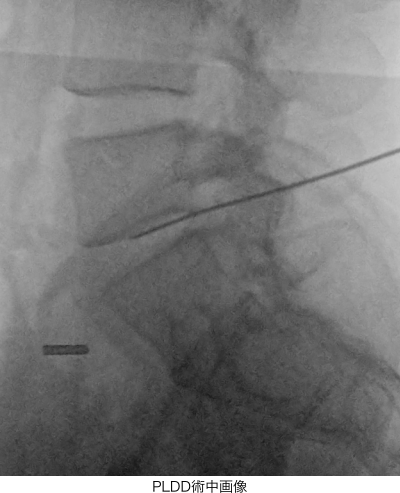

- PLDD(経皮的レーザー椎間板減圧術)

「PLDD(経皮的レーザー椎間板減圧術)」は、背中からレーザーファイバーが通った針を刺し、椎間板の内部にレーザーを照射してヘルニアの縮小を目指す治療です。